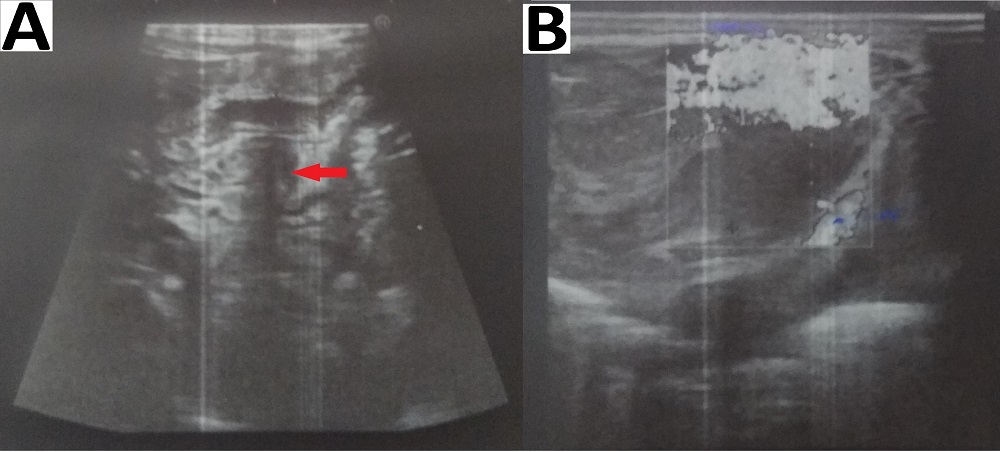

Figure 4

Photographs showing abdominal ultrasound scans performed after pyloromyotomy (Group A) with intraperitoneal blood collection (red arrow) around the pylorus (red arrow; A) and collection in Morrison’s pouch (B).

Figure 5

Photographs showing abdominal ultrasound scans performed after pyloromyotomy (Group B) with oxidized regenerated cellulose gauze patch represented by hyperechogenic line (red arrow); minimal fluid (+) around the pyloromyotomy site is also present (B).

One patient in our study who developed ileal perforation, presented after discharge with features of peritonitis (5 days postoperatively); the diagnosis was established intra-operatively during the second surgery. The cause of ileal perforation was not known, but likely due to iatrogenic injury. The trace of pyloromyotomy was represented by a faint furrow with a light yellow white, slightly edematous serosa (Fig. 3). One patient in group A with intraperitoneal blood collection (above mentioned) required blood transfusion for anemia caused by pyloromyotomy-site bleeding. The diagnosis was established by ultrasound abdomen (Fig. 4). In cases with postoperative vomiting, ultrasounds were performed to diagnose complications or those related to the placement of Surgicel®, which were normal (Fig. 5).